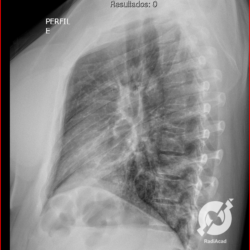

E o nome dado a esta alteração radiográfica que corresponde à substituição do ar alveolar por líquido é a consolidação alveolar.

Uma consolidação alveolar é, por definição, uma opacidade (imagem densa, branquinha) homogênea ou às vezes heterogênea (pela presença de calcificações ou cavidades), de limites mal definidos, exceto quando toca a pleura da parede ou das cissuras pulmonares. É um termo usado tanto em radiografia, como em tomografia computadorizada. Na tomografia, um outro termo é usado: vidro fosco, que é uma opacidade (branquinha mas não tanto como a consolidação), que borra o pulmão mas deixa ver os vasos de permeio (igual bigode de adolescente: dá pra ver todo o fundo).

Nós vamos mostrar aqui um pequeno apanhado de pneumonias de variados agentes, em diversos segmentos e lobos pulmonares, com extensões variadas. O objetivo é identificar o padrão radiológico de consolidação alveolar e não determinar o agente infeccioso, isso vai ser assunto para mais adiante. Aliás já antecipo que é fundamental saber localizar a lesão, porque alguns destes bichos gostam de determinados segmentos, alguns tumores também têm as suas preferências, então localização é fundamental. Se localização não fosse importante, um apartamento na beira do mar sairia o mesmo preço de um apartamento de frente pra BR-101, concordam?

Seguem alguns dos nossos casos de pneumonia para vocês treinarem os olhos e não se apavorarem nos plantões.